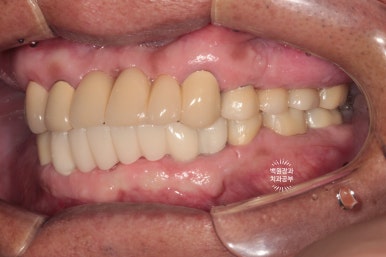

위 어금니와 아래 앞니가 없는 상태입니다.

보시면 아주 최소한의 치아만 닿고 있는게 보이시죠?

성인 남성의 턱 힘을 견뎌내기에 무리가 있어요. 그래서 치아가 자꾸 깨져나가게 되지요.

신경치료를 받은 어금니들에게 임시치아를 제작해주었습니다.

아래 앞니 부위는 임플란트 1차 수술을 시행하였습니다.

신경치료를 받고나면, 치아 가운데에 구멍이 생겨 치아가 구조적으로 약해집니다.

이를 보강하기 위해 임시치아를 제작해 드렸었어요.

그러면서 기다리는 동안 잘 아물은 아래 앞니쪽에 임플란트를 심어드렸습니다.

치료가 잘 되어있는 것이 보이고, 슬슬 윤곽이 잡혀가네요!!

임시치아를 먼저 제작해드렸습니다.

시간이 흘러 잇몸이 아물고 위 임플란트의 임시 보철물을 제작해 드렸습니다.

왼쪽은 임플란트에 맞춤형 지대주 (custom abutment)를 연결한 사진이고,

오른쪽은 그 맞춤형 지대주에 임시치아 (temporary crown)을 접착한 사진입니다.

이제 슬슬 치료가 끝나가는게 보이실거에요!

색상이 다소 맞지 않습니다만, 이는 플라스틱 재질과 비슷한 임시치아이므로 기능을 잘 하실 수 있는지 평가하는데 집중해봅니다.!!

양쪽 어금니가 잘 물리고 이제 밥을 먹을 수 있어요.

이렇게 얘기하시면 이제 치료의 끝이 보이는겁니다.ㅠㅠ